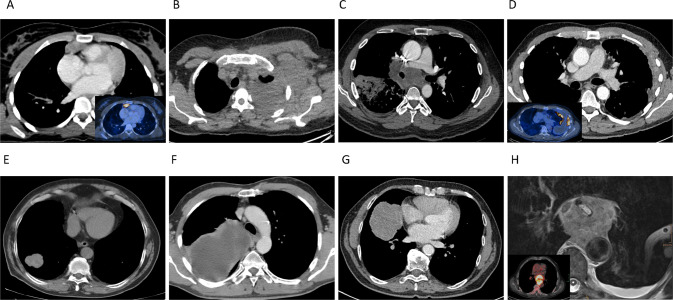

In total, we identified nine intrathoracic neoplasms with immunohistochemical loss of INI1 (SMARCB1) (Supplementary Table 1), of which all were initially classified as intrathoracic neoplasms from either the lung (N = 3), lung/pleura (N = 1), pleura (N = 2), pleura/thoracic wall (N = 1) or mediastinum (N = 2). Patient information, clinical characteristics and original diagnoses are listed in Table 1. In our cohort, immunohistochemical INI1 (SMARCB1) deficient thoracic neoplasms occurred in one woman and eight men, ranging from 20 to 76 years of age (mean 57 years) at disease presentation. Smoking history was reported in six patients, ranging from 10 to 80 pack years (mean 34 pack years). For one patient smoking status was not available (patient 5) and 2 patients were documented as never-smokers. Based on computer tomography scans in eight patients, the tumors presented as lung (N = 3), lung/pleura (N = 1), pleura (N = 2), pleura/thoracic wall (N = 1) or mediastinal (N = 2) masses (Fig. 1). In one case (patient 2) the pleural mass further involved the thoracic wall and axilla, this patient presented with extensive repetitive pleural effusions positive for malignancy. The tumor sizes at presentation ranged from 3.5 to 15.8 cm (mean 7 cm). Imaging and clinical follow-up information were obtained for all nine patients, with a median follow-up of 14 months (range 1–53 months). All nine patients died of progressive disease, one patient (patient 5) was lost to follow-up due to an early transfer to another hospital (Table 1). Metastatic disease at presentation occurred in five patients, with four having lung or pleural involvement only. Two patients showed distant metastases in bone, soft tissue, liver and adrenal glands (patient 1 and 6). No brain metastases were documented in any of the nine patients. For therapy, the chemotherapy regimens varied, reflecting the original heterogeneous diagnoses of carcinoma, mesothelioma and sarcoma. The original diagnoses were mostly made in concordance with their particular anatomic site, all were, however, interpreted as high-grade malignancies (Table 1). Patient 1 initially presented in an outside hospital and was diagnosed with a thymic squamous cell carcinoma. The case was referred to us for molecular testing, which revealed a SMARCB1 (INI1) homozygous loss that was accompanied by INI1 (SMARCB1) - loss in the complementary immunohistochemistry. Following re-evaluation by a soft tissue pathologist, the diagnosis of an epithelioid sarcoma, proximal type was concluded. The patient died of progressive disease 16 months after the initial presentation. Patient 4 died of localized disease within one month of initial presentation. Patient 9 was difficult to interpret as from a clinical presentation the tumor was located in the posterior mediastinum, growing almost circumferential around the esophagus. The patient passed away 4 months after initial presentation. Additionally, there were two cases (patient 4 and 7) with mainly in the pleural located neoplasms, none of which has a history of known asbestos exposition.

Fig. 1. Representative computer tomography images of 8 patients, illustrating tumor localization and extension.

A Patient 1: tumor localized in the anterior mediastinum (insert PET-CT scan). B Diffuse involvement of the thoracic wall with extension into the left axilla (patient 2). C, E, G Intrapulmonary localized tumor in patient 3, 6, 8, and 5 (not shown). Involvement of the pleura in patient 4 and 7. D, F Patient 9: tumor localized in the posterior mediastinum (insert PET-CT scan) (H).